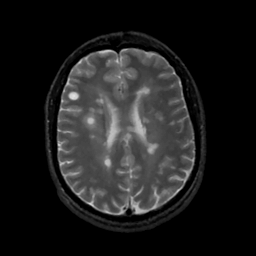

MR Study #1, February 10, 1991 -- Slice #32